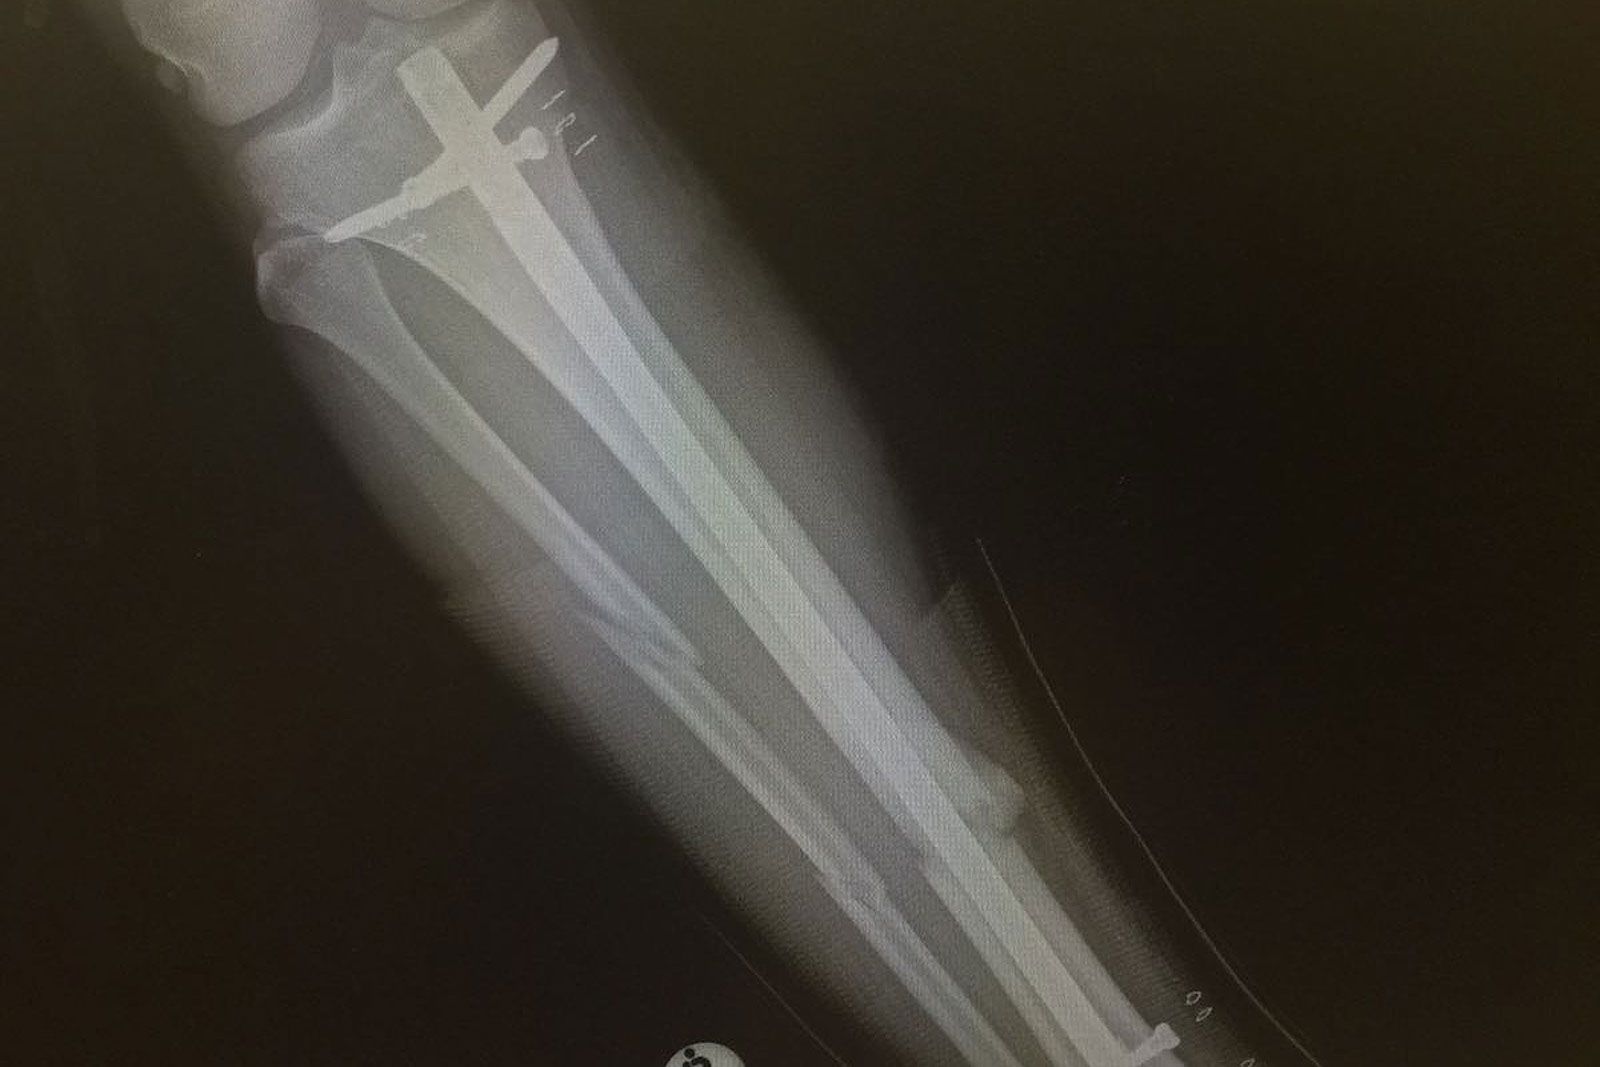

von Lars NiggemeyerLetztes Jahr konnte Alessio Stillrich seine bisher beste Saison auf der PWA Wave-Worldtour feiern. Das erste mal in seiner Karriere brach der 23-jährige Deutsch-Kanario in die Top-10 der Welt ein. Schon bei seinem Worldcup-Debüt an seinem Homespot Pozo Izquierdo auf Gran Canaria in 2009 hatte er für Aufsehen gesorgt. Niemand hatte bis dato derart verdrehte Tweaked-Pushloops in solcher Höhe gesehen, wie Stillrich sie zeigte. Seitdem hat er sich konsequent weiterentwickelt und sich - seitdem er Voll-Profi ist - jedes Jahr in der Weltrangliste weiter nach oben gearbeitet. Leider ist Stillrichs nächste Saison nun komplett in die Binsen gegangen. Im südafrikanischen Kapstadt zog er sich beim Training einen komplizierten und überaus schmerzhaften Beinbruch zu. Sechs Monate darf er nicht aufs Wasser. Im WINDSURFERS Interview berichtet Alessio über seinen Unfall.

Nach Meinung meines Arztes verläuft die Genesung nach Plan. Leider brauchen Schien- und Wadenbein vier Monate um wieder zusammenzuwachsen. Reha mache ich natürlich täglich und wir merken meine Fortschritte von Tag zu Tag. Ich bin in der Wohnung nach dem Okay vom Arzt schon ohne Krücken unterwegs. Schwimmen darf ich auch schon seit ein paar Wochen. Es geht also aufwärts, obwohl es schwer ist die Geduld zu bewahren.